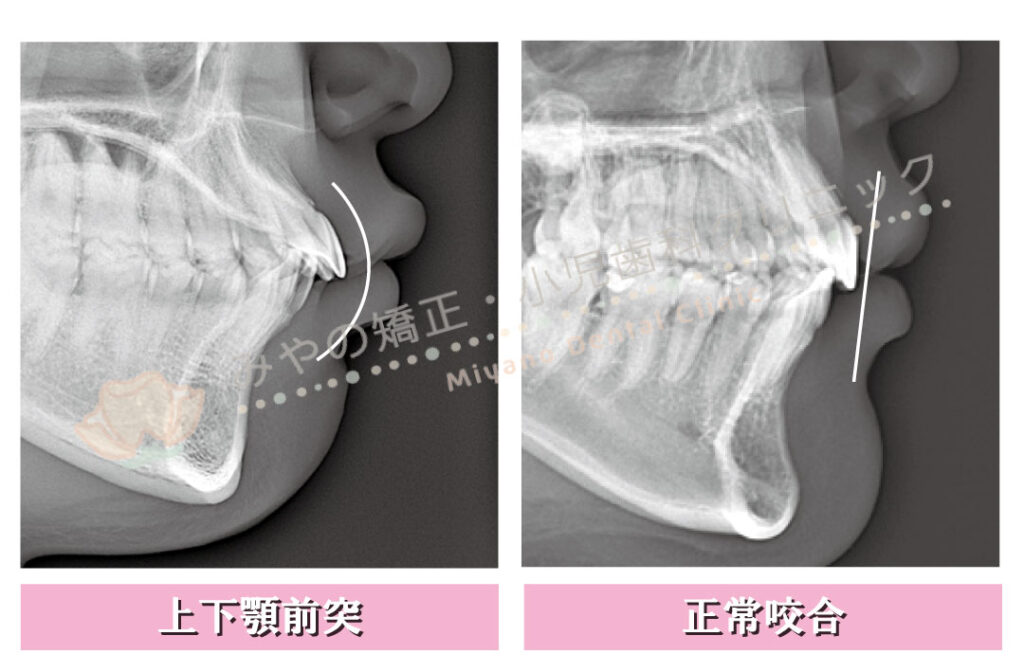

口元がでている・口ゴボ・ゴリラ顔のような表現をされるかみ合わせを正式には上下顎前突と呼びます。

上下の前歯の角度が小さく、上下の歯が前に突出しているかみ合わせです。

正常では上下の前歯の角度は130°くらいですが、上下顎前突の場合は上下の前歯の角度がより鋭角になります。